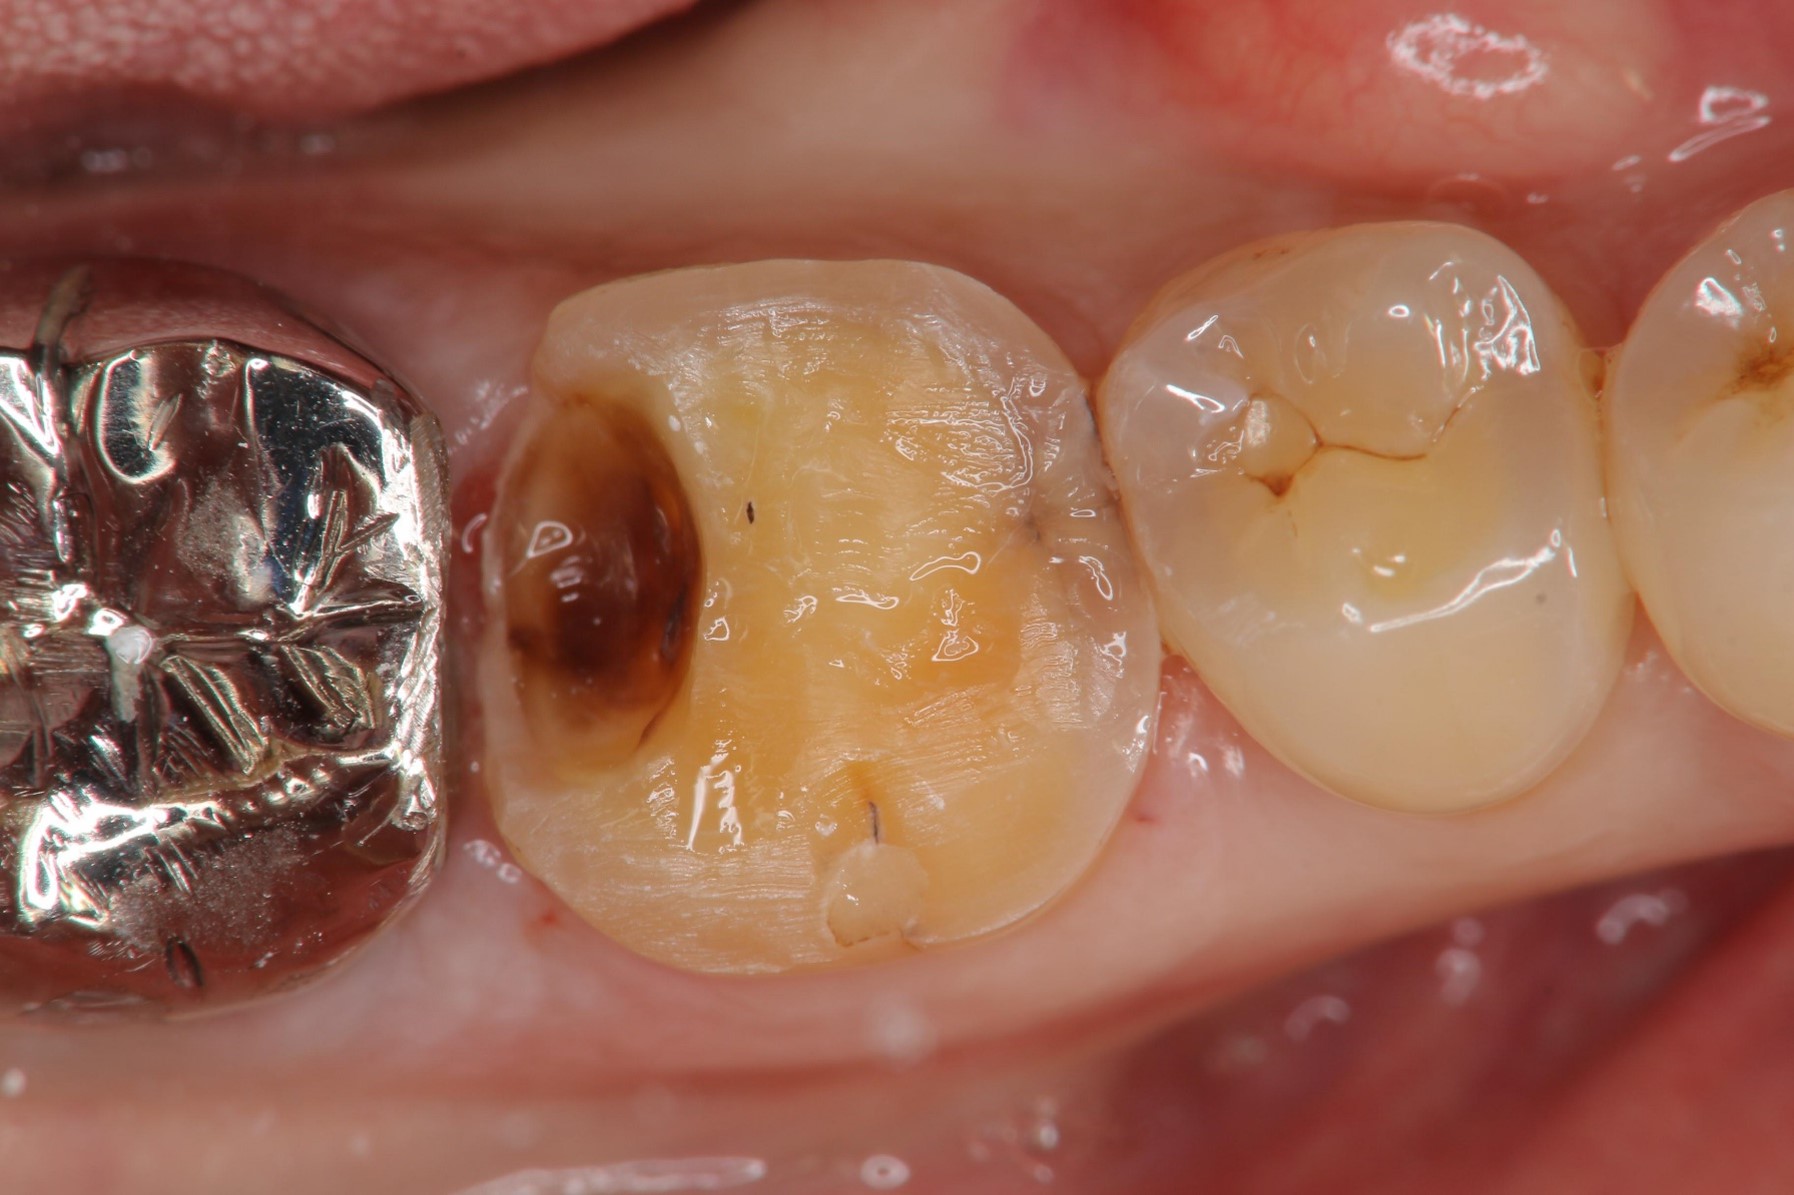

治療前,嚴重蛀牙,咬頭受損

蛀牙未到牙髓

冠塊體體製備